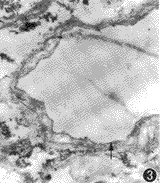

电镜下观察:脂肪细胞呈中等电子密度,核不明显;成纤维细胞核呈高电子密度,边界不清或染色质轻度聚集呈网状,无细胞膜包裹(即胞膜消失),胞质内细胞器结构不清;胶原纤维束中,原纤维可见,但横纹不明显;血管可以依管壁区分小动脉及小静脉,内皮细胞及血管壁其他细胞成分结构不清,仅见细胞轮廓(图2~4)。

图3,4 箭头示植入物中的小静脉及小动脉,内皮细胞及血管壁其他细胞

成分结构偿清,仅有管壁轮廓 ×900 三、手术方法